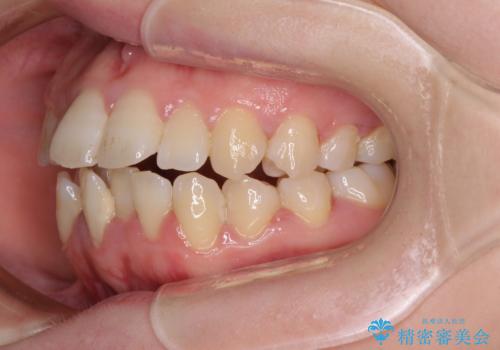

上下非接触で突出した前歯 ワイヤー装置による抜歯矯正

- 上下前歯の隙間と口元の出っ張った感じを気にして来院された患者様です。

上下の隙間は舌突出癖によるもので、またその癖により前歯が前方に出ている状態でした。

口元の出っ張りを改善するため、上下左右第一小臼歯4本を抜去し、ワイヤー装置にて矯正治療を行うこととしました。